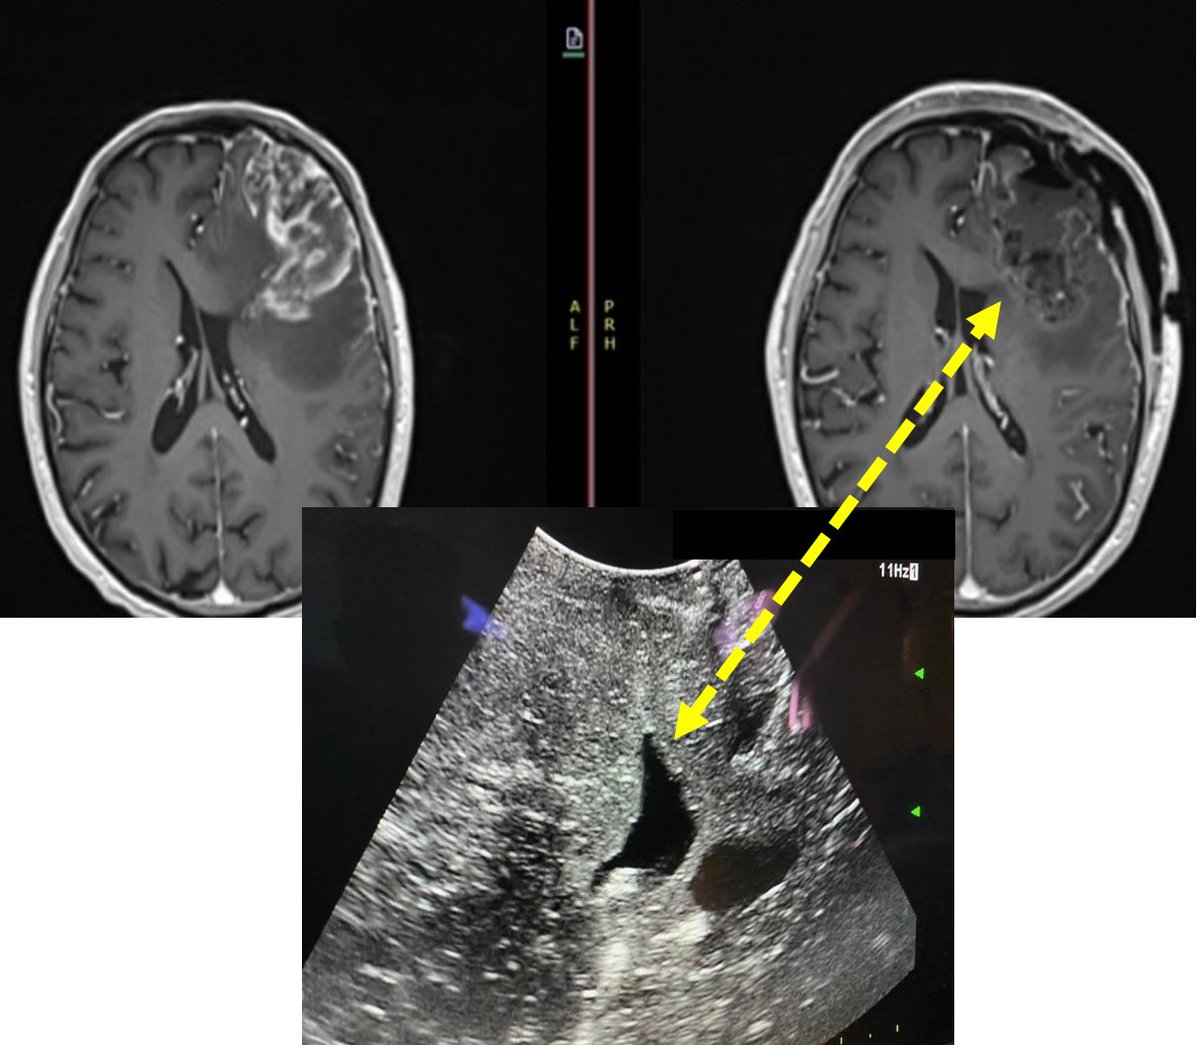

Intraoperative Ultrasound is a very useful realtime tool to check on the tumor complete resection. In this case prevented us to open the ventricle and decreased the risk of malignant tumor cells dissemination into the CSF (patient consented) @theABTA @dr_mmandel @DrBadihAdada

English